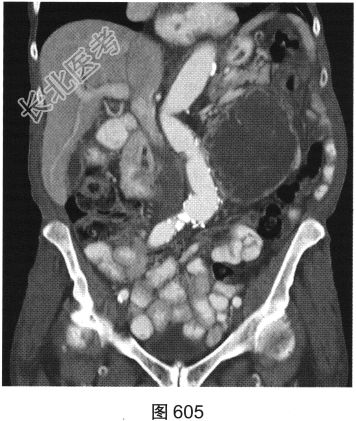

- [材料题] 患者女性,85岁,腹主动脉瘤破裂手术修复后,腹部疼痛。患者行腹部CT检查,见图603~图607。

- 多项选择题1.对该病变CT影像表现描述正确的是( )

A、腰大肌未见明确异常

B、未见主动脉再破裂征象

C、可见主动脉再破裂

D、可见腹膜后均质肿块

E、腰大肌受累

F、可见腹膜后不均质肿块

- 多项选择题2.若CT发现该病灶,建议下一步进行哪项检查最合适( )

A、穿刺活检

B、PET

C、超声

D、血管造影

E、随诊复查

F、MRI